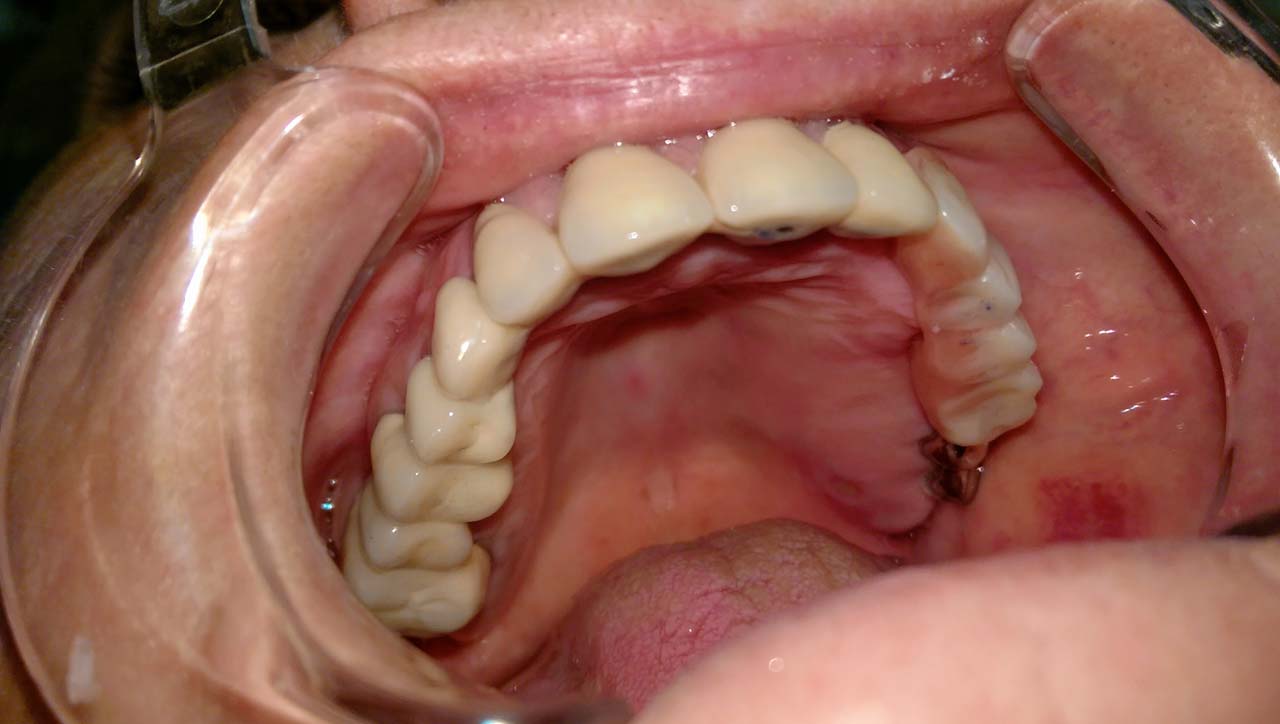

Elhanyagolt fogsor cseréje 2 nap alatt

2 nap alatt varázsoltuk ezt a szép esztétikus alsó, felső körhídat implantátumokkal megtámasztva a korábban elhanyagolt szájba. Az 1. nap 26 fogat távolítottunk el, mert annyira rossz állapotban voltak, és rögtön azonnal terhelhető IHDE svájci implantátumokat raktunk be, fentre 8, lentre 6 darabot. A sebeket összevarrtuk és intraorális szkennerrel digitális lenyomatot vettünk. 2 nap múlva pedig beragasztottuk a kész PMMA műanyag körhidakat. Dr. Kelemen Péter és a Symbion Fogtechnika munkája.